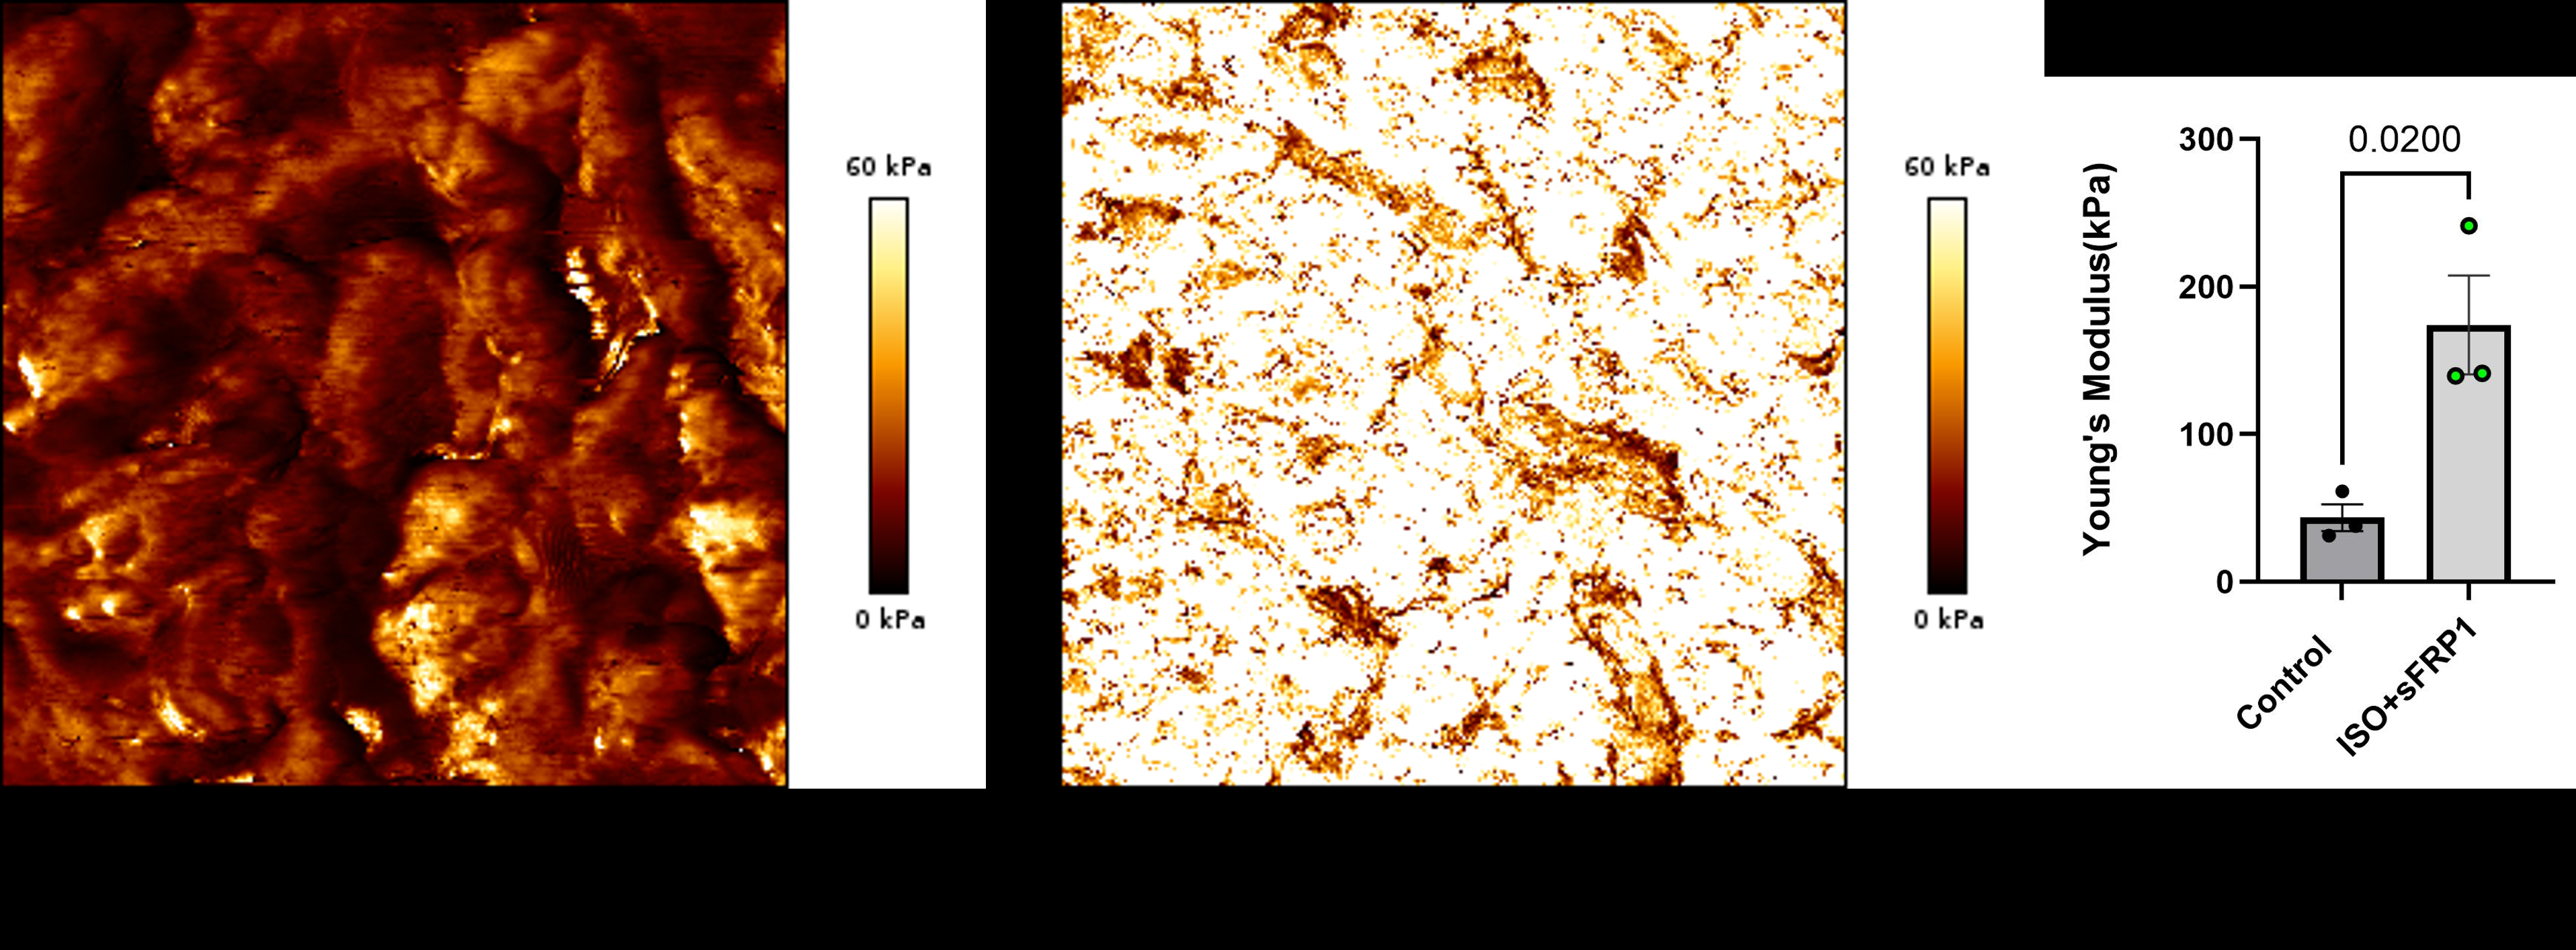

In vitro and In vivo approaches were used. Neonatal rat ventricular myocytes and neonatal rats were injected intraperitoneally with vehicle control, ISO +/- sFRP1. We evaluated cardiac function, performed bulk and single nuclei RNA-sequencing, metabolomics, and measured tissue stiffness by Atomic Force Microscopy.

Our results show that sFRP1+ISO promotes DCM (Figure 1), which is associated with increased stiffness (Figure 2) but not fibrosis or hypertrophy. Importantly, we also observed increased stiffness in pediatric DCM hearts. Also data from our in vitro and in vivo experiments (including next generation sequencing) suggest ISO+sFRP1 activates Notch (Figure 3) and promote pathologic remodeling in a novel, inter-dependent manner similar to data from human pediatric DCM.